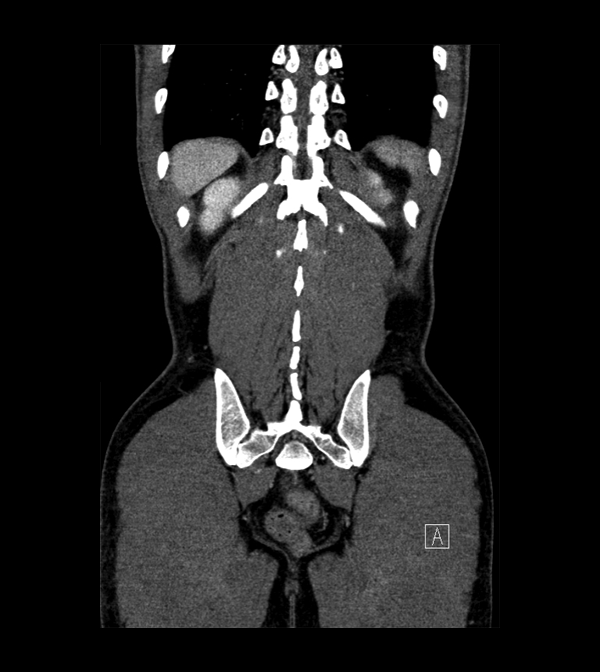

Body

Covers abdominal CT anatomy.